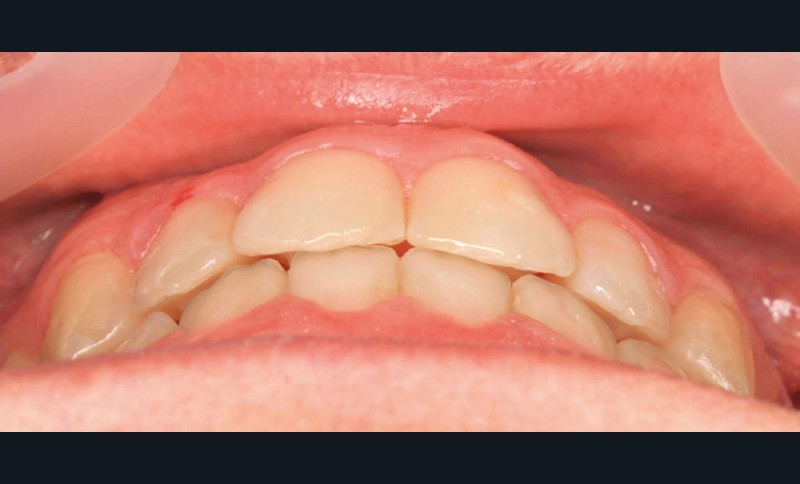

Diagnostic (fig. 1a-g)

La patiente présente une classe III squelettique dans un contexte hyperdivergent associée à une endoalvéolie maxillaire, un articulé inversé antérieur, une rétroversion incisive maxillaire, des rapports de classe I canine bilatérale, une absence de 16 et 36.

Au niveau esthétique, le profil est rectiligne. La lèvre supérieure est plus effacée, en retrait par rapport à la lèvre inférieure. De face et de profil, la mandibule paraît massive et le maxillaire effacé : le manque de soutien de la lèvre supérieure contribue à cette impression.

Le sourire est étroit, dégradé par les malpositions dentaires.

Au niveau fonctionnel, il existe un pro-glissement mandibulaire et un articulé inversé antérieur. Le profil téléradiographique montre en occlusion des rapports labiaux et un profil de classe III plus marqué que sur photographies.